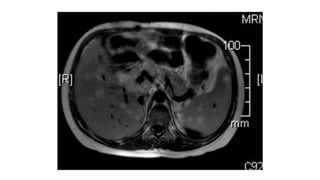

Resonancia Magnetica

• Se utiliza en pacientes con falla renal significativa o en pacientes

alérgicos al contraste.

Resonancia Magnetica • Seutiliza en pacientes con falla renal significativa o en pacientes alérgicos al contraste.